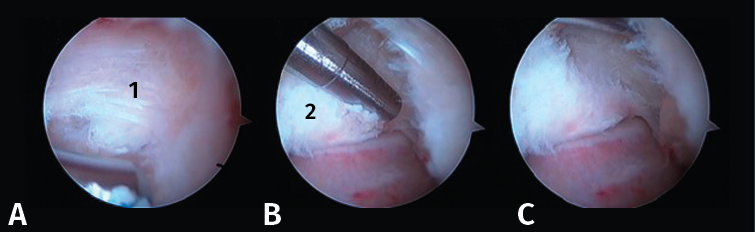

Figura 4. A: imagen artroscópica que muestra el ligamento peroneo-astragalino posterior (LPAP) (1); B: resección del LPAP con un sinoviotomo orientado medialmente contra la cara lateral del proceso posterolateral del astrágalo (PPA) (2); C: cara lateral del PPA después de la resección del LPAP.

- Primer paso: retirar el LPAP, completamente en caso de PPAH y parcialmente en caso de OT. La resección del tejido ligamentoso se realiza apoyando la ventana del sinoviotomo contra el lateral del PPA (Figuras 4 A, B y C).